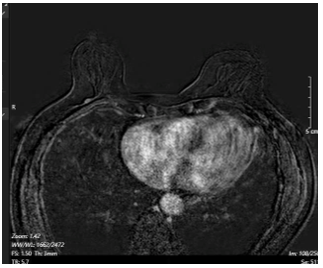

- Cộng hưởng từ tuyến vú có tiêm tương phản: Hình ảnh đám ngấm thuốc trung tâm vú phải, không tạo thành khối, dài 43mm, vùng tổn thương 15x15mm, trung tâm tổn thương dưới núm vú 22mm, nhưng tổn thương ngấm thuốc tới tận núm vú, núm vú ngấm thuốc mạnh (BIRADS 6). Tổn thương chưa xâm lấn cơ thành ngực. Hạch trong nhu mô vú phải vị trí 8h, cách núm vú 6cm, kích thước 4x6mm,ngấm thuốc từ từ tăng dần. Không thấy bất thương vú trái (BIRADS 1).

Hình 3:

Hình ảnh cộng hưởng từ tuyến vú có tiêm tương phản. Hình ảnh đám ngấm thuốc trung tâm vú phải đã lan tới núm vú (BIRADS 6) (mũi tên màu xanh dương).

- Cộng hưởng từ tuyến vú có tiêm tương phản:

Hình 6. Hình ảnh cộng hưởng từ tuyến vú có tiêm tương phản: Hiện không thấy tổn thương nghi ngờ ác tính trên phim cộng hưởng từ tuyến vú hay bên/ Sau điều trị có đáp ứng hoàn toàn.